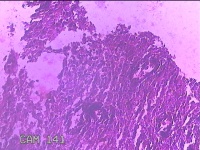

颈部肿物

性别

男

年龄

57岁

临床诊断

纤维瘤病;皮肤感染

一般病史

面部起疹3月,不痒。

标本名称

大体所见

灰白粉红色肿物0.3x0.2x0.1cm一个,表面光滑。

图7

图8

图10

图12

图13

图14

图15